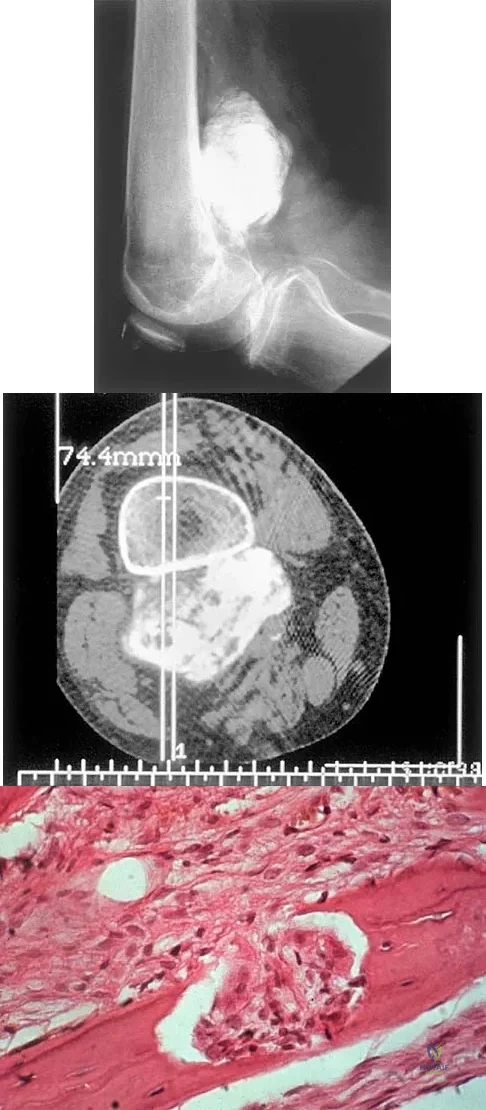

Question 24

A 10-year-old boy has had wrist pain for the past 3 months. He denies any history of trauma. He reports mild tenderness associated with a palpable mass. A radiograph and biopsy specimens are shown in Figures 52a through 52c. What is the most likely diagnosis?

Explanation